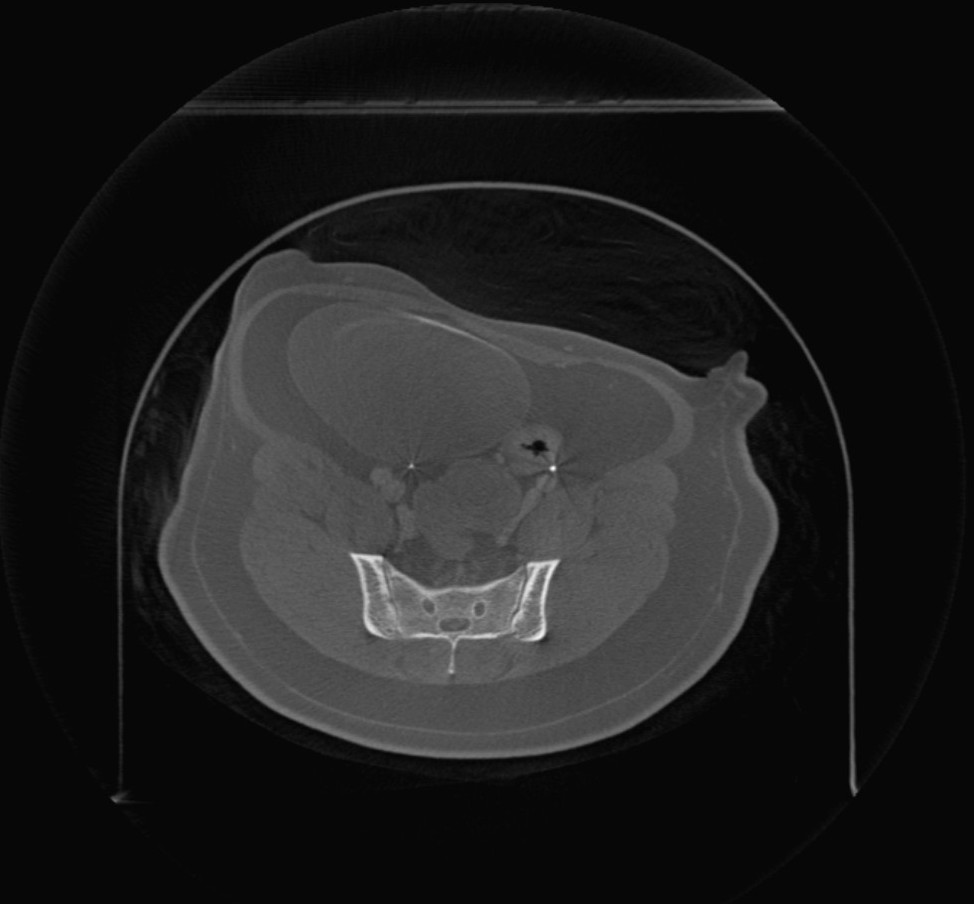

Volumetrikus DICOM képek (CT és MR modalitás) megnyitásakor a Megjelenítő felső eszköztárában egy további menü érhető el (Képsíkok) néven. A kép orientációjának módosításához válassz a három elérhető sík közül: (Axialis, Koronális és Saggitális).

A kiválasztott sík befolyásolja a CT/MR szeletek helyzetét és orientációját, valamint azok 2D síkon történő rekonstrukcióját.